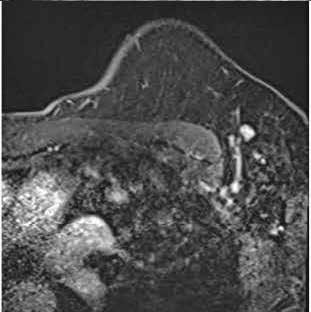

Figura 3.

Resonancia magnética. Secuencia T1 y T2. Cortes sagital y transversal. Estudio artefactado por el movimiento del paciente. Estudio T1 donde se aprecia una lesión hipointensa con moderada restricción a la difusión en las capas medias del esplenio del cuerpo calloso, que en la secuencia T2 corresponde con una lesión hipertensa. Esta lesión en dicha localización y en el contexto clínico del paciente es altamente sugestiva de Marchiafava-Bignami.

Figura 4. Resonancia magnética cerebral a los 8 meses. Secuencias T1, T2 y difusión, corte sangital y transversal. En el esplenio del cuerpo calloso se observa adelgazamiento, con presencia de un área de necrosis en las capas medias de hiperintesidad de señal periférica con aumento de difusividad. En comparación con RM previe se objetivan cambios evolutivos con necrosis, atrofia y aumento de la difusión. Hallazgos compatibles con la enfermedad de Maarchiafava-Bignami.